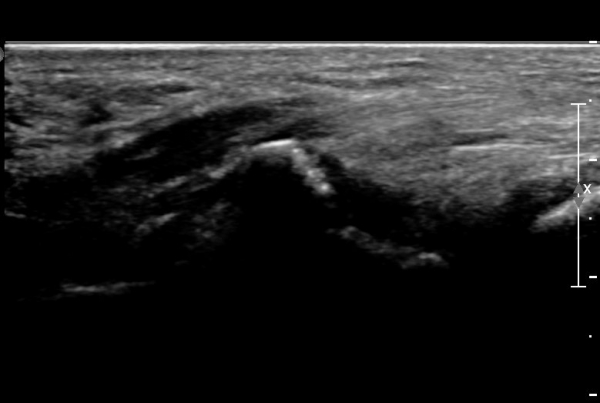

ŽÃËÀÚ¸¦ ¾à°£ ¸»´ÜÀ¸·Î À̵¿ÇÏ´Ï ¿¬ºÎÁ¶Á÷ ºÎÁ¾ÀÌ ´õ¿í ½ÉÇÏ°Ô °üÂûµÇ°í(»çÁø 2),

Á¶±Ý ´õ ¸»´ÜÀ¸·Î À̵¿ÇÏ´Ï Äá¾Ë»À ÇÇÁú°ñ ¿¬¼Ó¼º ¼Ò½ÇÀÌ °üÂûµÊ(»çÁö 3),

Äá¾Ë»À Á¾´Ü¸é°Ë»ç¿¡¼­ Äá¾Ë »À ±ÙÀ§ºÎÀÇ ÇÇÁú°ñ °ß¿­ÀÌ °üÂûµÊ(»çÁö 4).